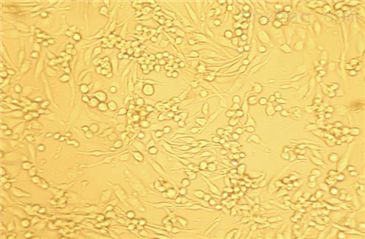

细胞形态:上皮样

细胞特性:该SK-OV-3由TrempeG和OldLJ在1973年从一位64岁白人女性卵巢腺癌患者的腹腔积液分离得到。该细胞对肿瘤坏死因子和几种细胞毒性药物(包括白喉毒素、顺铂和阿霉素)耐受。在裸鼠中成瘤且形成与卵巢原位癌一致的中度分化的腺癌

细胞纯度:91%

细胞活力:92%(ViabilitybyTrypanBlueExclusion)